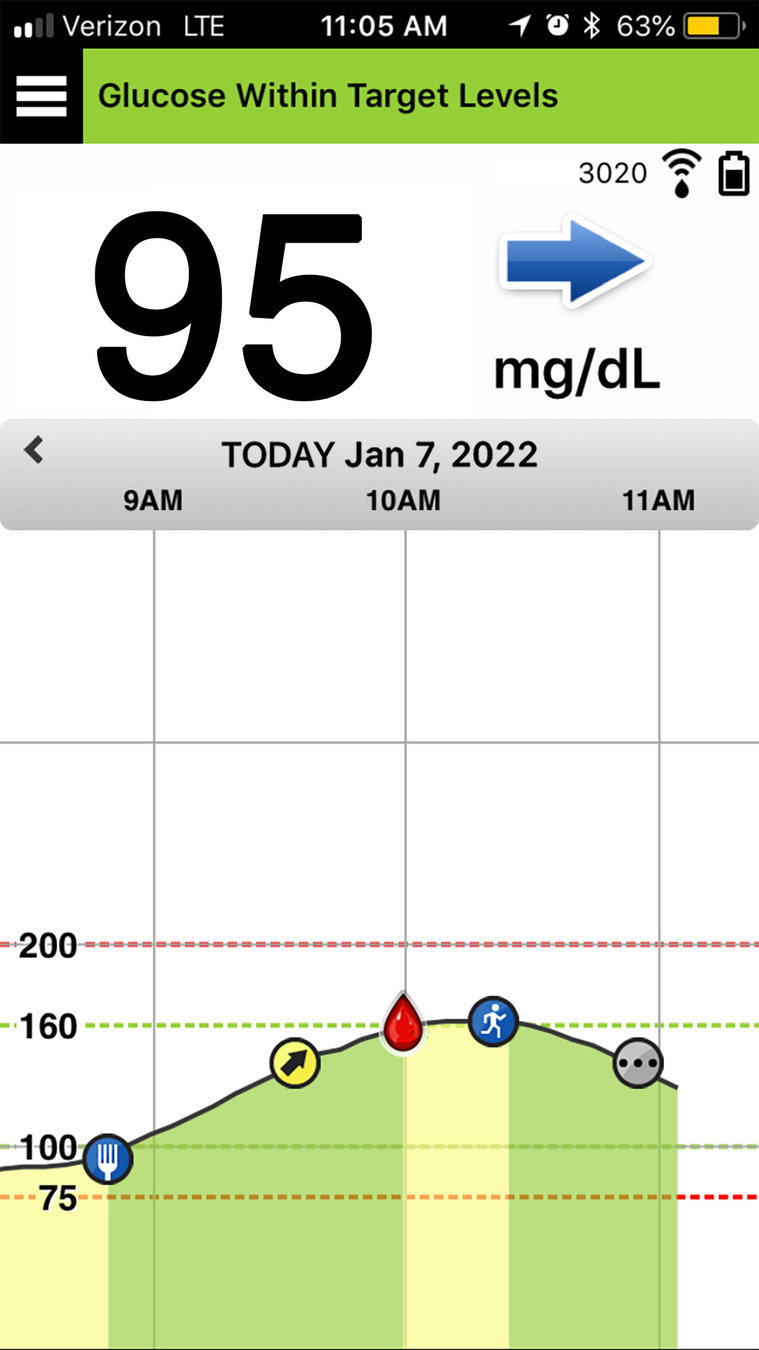

Aquí puede ver un ejemplo. Supongamos que está a punto de comer y que está calculando su dosis de insulina.

Mira la aplicación Eversense® y ve que su nivel de glucosa es de 95 mg/dL y que la flecha de tendencia está plana. Esto quiere decir que su nivel de glucosa está actualmente estable, por lo que es probable que no sea necesario ajustar su dosis normal de insulina antes de las comidas.

FLECHAS DE TENDENCIA